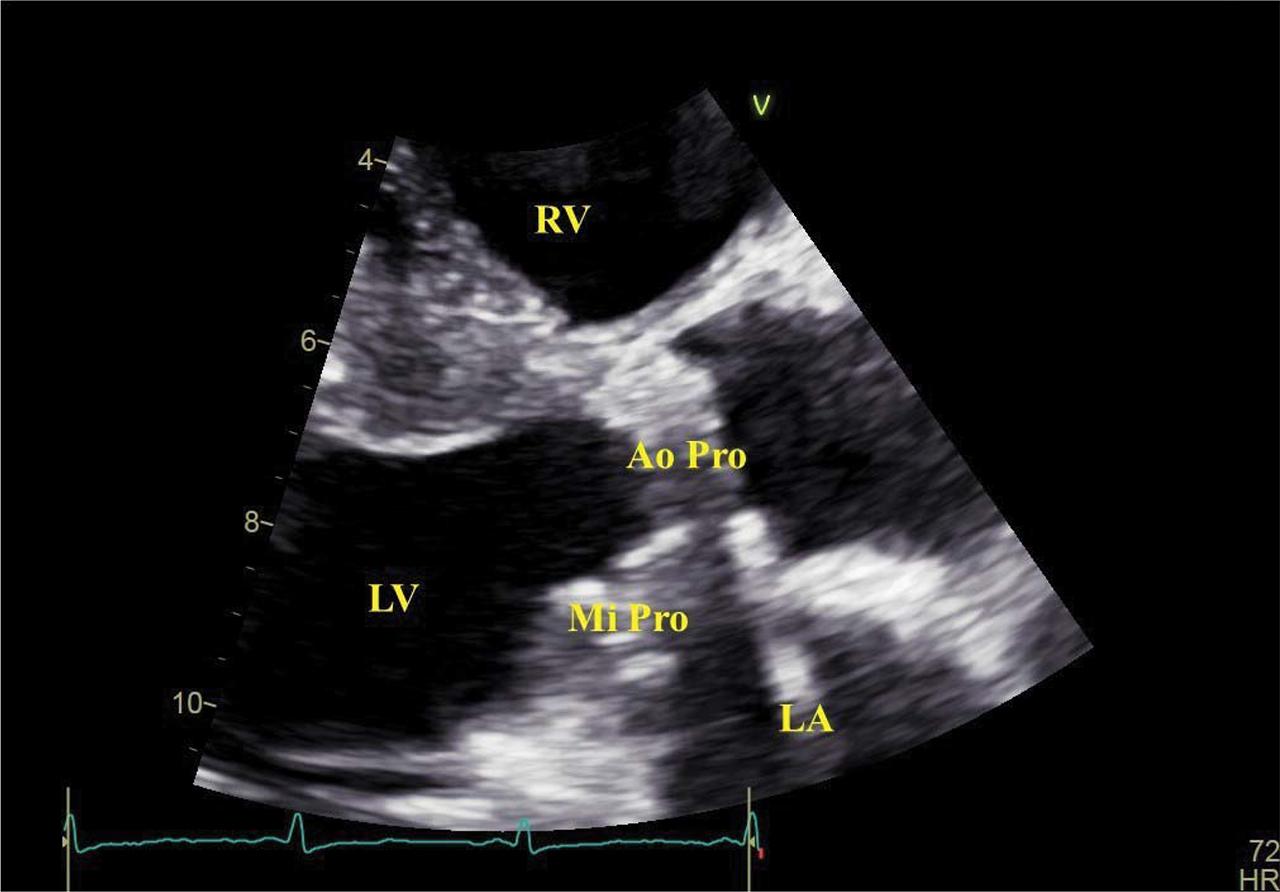

Figure 1